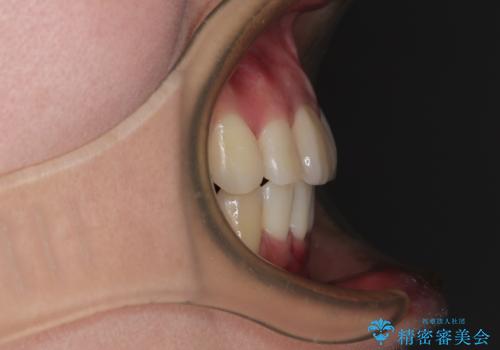

- 八重歯と上の前歯が出っ歯になっていることを気にして来院された患者様です。

横から見た際の口元の飛び出した印象も改善したいとのことで、上下左右の第一小臼歯4本を抜歯し、ワイヤー装置にて抜歯矯正を行うこととしました。